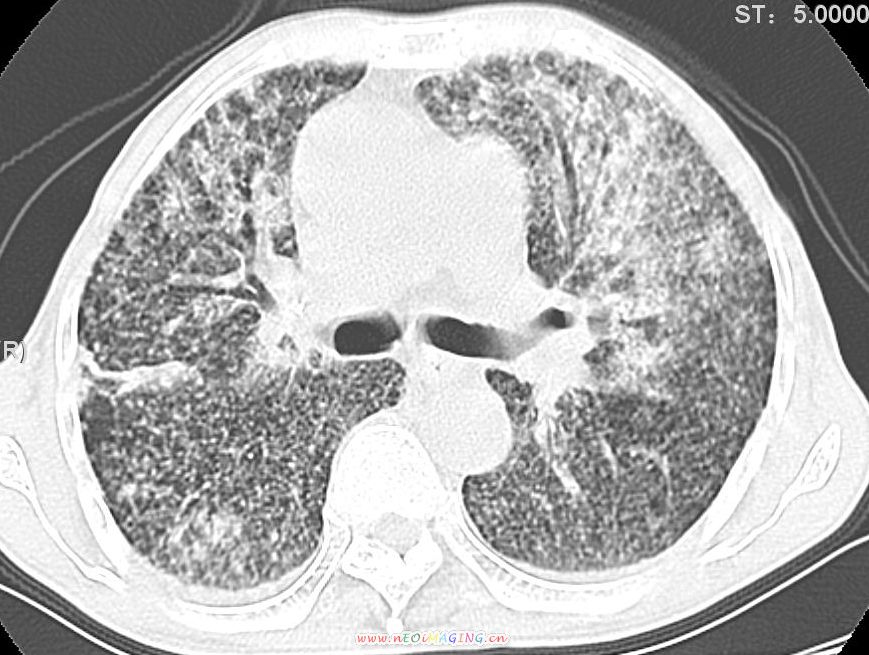

患者咳嗽月余,高热数天,咳黄色稍脓痰。

双肺野分布多个小结节状高密度影,其内散在斑片状模糊影,气管。支气管通畅,纵隔内淋巴结钙化,胸膜局限性增厚粘连,胸腔少量积液。结合病史考虑结核并感染的可能性大,胸膜炎并积液。肺泡癌待排。

纵隔内见钙化的淋巴节,上肺见钙化灶,双肺均匀弥漫分布小结节影,边缘较清楚,能不能考虑是在矽肺的基础上并发的结核和感染,请详细了解病史结合临床.